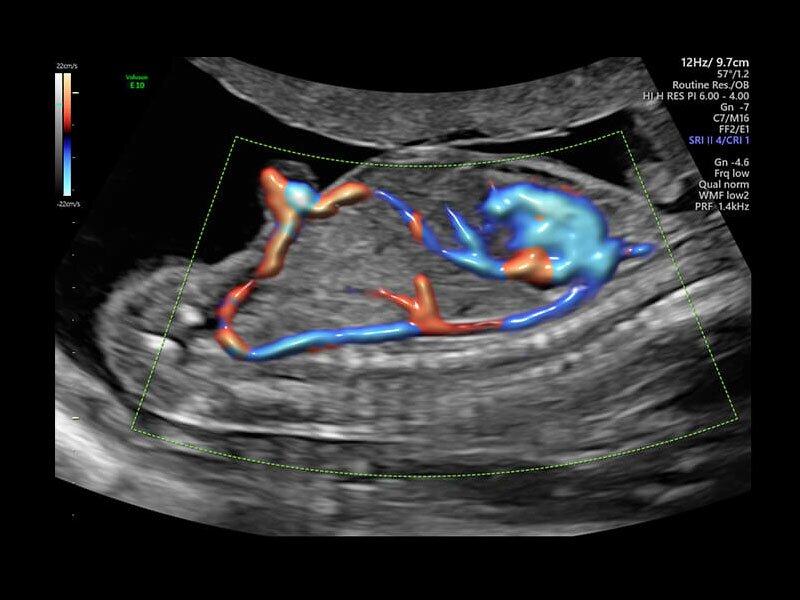

Клинические изображения

• Высокочувствительный допплер (HD-Flow)

• Реалистичный объёмный кровоток в режиме ЦДК (Radiantflow)

• HDlive Flow - перемещаемый источник света, совместимый с визуализацией кровотока в 3D

• HDlive Flow Silhouette - режим "Силуэт" с выделением границ полостей сердца и сосудов, совместимый с визуализацией кровотока

• Advanced STIC - расширенный программный пакет для исследования сердца плода в режиме 4D для механических и электронных объемных датчиков:

• Использование цветного, энергетического допплера, В Flow - режим STIC.

• Сочетание с М-режимом - STIC-M-Mode

• Перемещаемый источник света - STICflow

• SonoVCADHeart - программное обеспечение для исследования сердца плода в режиме 3D/4D (быстрый доступ к плоскостям сканирования) по рекомендациям ISUOG

Объемное сканирование Voluson — 3D/4D вашей мечты

Объемное УЗИ на Voluson E10 — это не просто потрясающе красивая картинка, это ценный инструмент получения дополнительной информации при обследовании женщин.

Voluson E10 поддерживает инновационные технологии формирования изображений — HDlive Silhouette и HDlive Flow, которые позволяют увидеть мельчайшие детали. Алгоритм SonoRenderlive упрощает рабочий процесс и дает возможность реконструировать изображение поверхностей, определяя область перехода между тканью и жидкостью.

• Технология HDlive Flow — повышает реалистичность визуализации сосудистых структур, улучшая восприятие глубины (по сравнению с традиционным цветовым допплером и функцией HD-Flow).